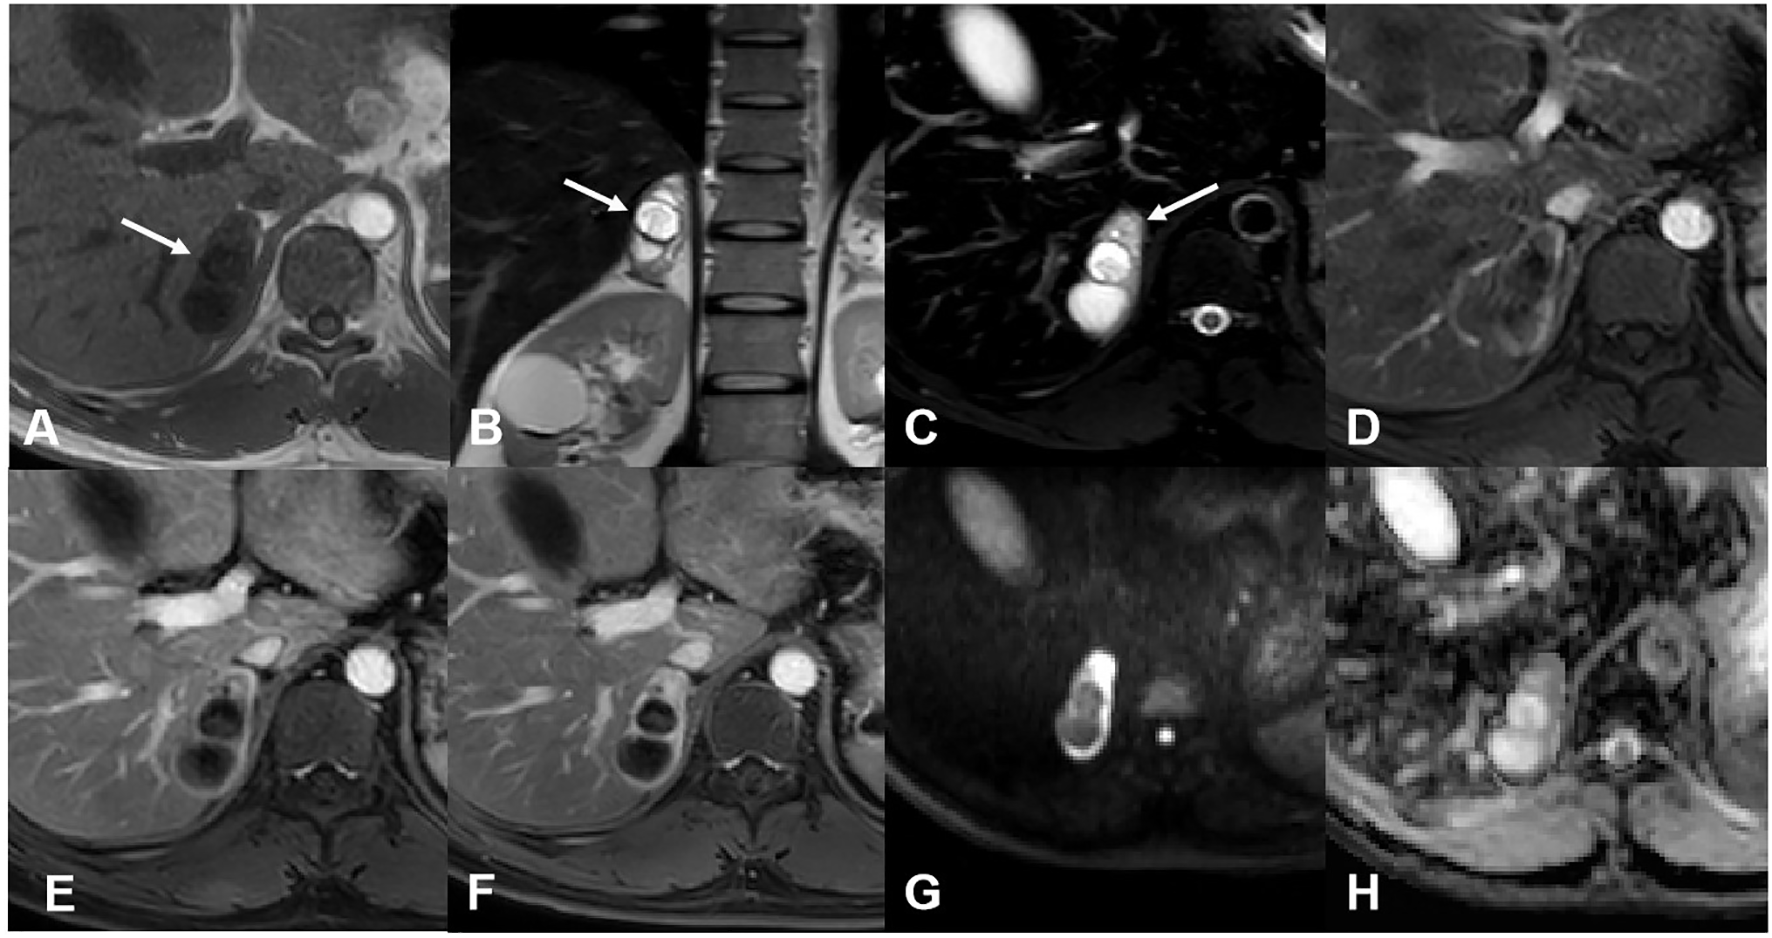

For case 1, MR images revealed a well-marginated, irregular mass measuring 5.2 cm × 2.4 cm in the right adrenal gland. The mass was mainly cystic, with a solid area in its more peripheral portion. The solid part was hyperintense on axial spectral attenuated inversion recovery (SPAIR) images and presented heterogeneous, marked enhancement after contrast administration, delineating the cystic area. There was no obvious restricted diffusion of the solid components (Figure 1). Based on the above findings, the radiologist suggested a schwannoma or a pheochromocytoma.

MR images of case 1. (A) The mass was hypointense on the T1-weighted image. (B) The T2-weighted image showed the mass was mainly cystic with some solid area in its more peripheral portion. (C) The solid area was hyperintense on the T2 SPAIR image (arrow). Enhanced images of arterial (D), venous (E), and delayed (F) phases showed gradual enhancement and delayed washout of the solid component. The cystic potion was not enhanced. Diffusion-weighted (G) and apparent dispersion coefficient (H) images showed no restricted diffusion of the solid component.